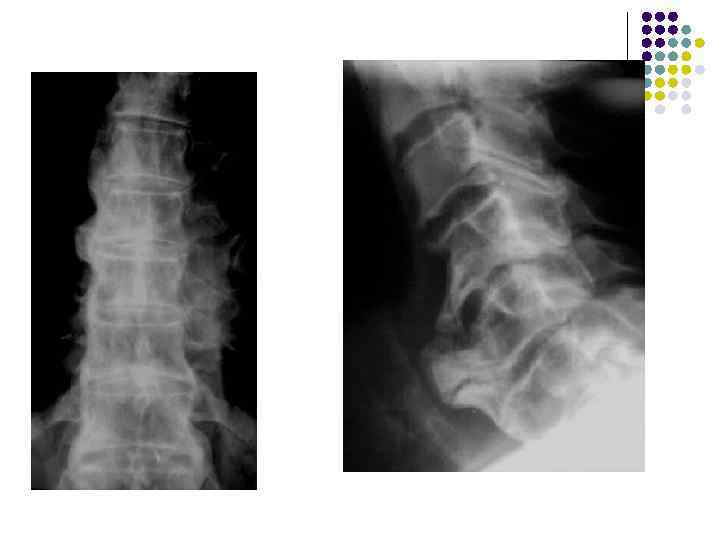

l l l На рентгенограмме шейного отдела позвоночного столба в боковой проекции определяется: выраженные распространенные дистрофические изменения в виде остеохондроза и артроза дугоотростчатых суставов: неравномерное сужение межпозвонковых пространств, субхондральный остеосклероз, костные разрастания по краям тел позвонков, сужение рентгеновских суставных щелей дугоотостчатых суставов с субхондральным остеосклерозом и небольшими костными разрастаниями по краям суставных поверхностей. Наиболее ярко эти изменения выражены в сегментах С 5 -6 -7 Признаки ограниченного смещения тел позвонков в виде симптома «распорки» и кифотической установки. Заключение: Остеохондроз шейного отдела позвоночного столба. Артроз дугоотростчатых суставов. Деформация шейного отдела позвоночника с нарушением статики.

1.

l l l На рентгенограмме шейного отдела позвоночного столба в боковой проекции определяется: выраженные дистрофические изменения за счет остеохондроза - значительное, неравномерное сужение межпозвонковых пространств с нарушением их правильной клиновидной формы, выраженный субхондральный остеосклероз, значительные костные разрастания по передним краям тел позвонков. Наиболее ярко эти изменения представлены в сегментах С-5, 6, 7. Помимо этого, в этих же сегментах фиксируются дистрофические изменения дугоотростчатых суставов – сужение рентгеновских суставных щелей, субхондральный остеосклероз и костные разрастания по краям суставных поверхностей. Выпрямление физиологического лордоза. Признаки системного нарушения статики тел позвонков в виде симптомов кифотической установки. Деструктивных изменений нет Заключение: Комплекс дистрофических изменений шейного отдела позвоночного столба в виде остеохондроза и артроза дугоотростчатых суставов с преимущественными проявлениями в нижних сегментах отдела. Нарушение статики тел позвонков

3.